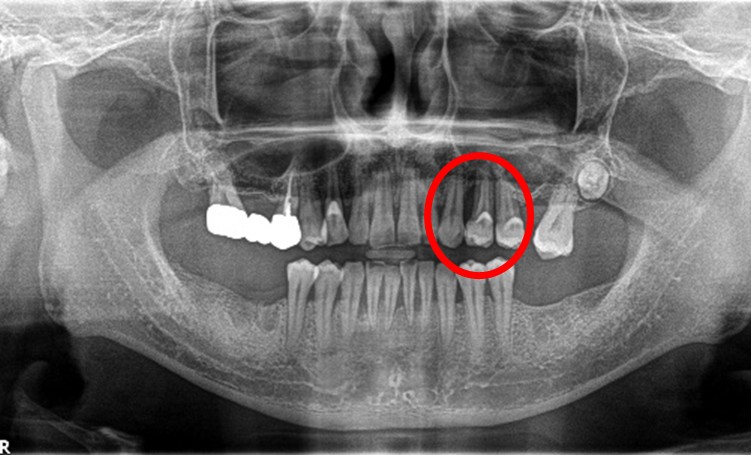

「右下の1番後ろの歯が浮いたような感じで、グラグラしていて噛むと痛みもあります。」とのこと。レントゲンで詳しく調べると、噛み合わせの問題と歯周病の進行が原因で、奥歯の周りの骨がなくなってしまっていました。この歯は残念ながら抜歯になることをYさんにお話しし、他の歯が多く残っているので、インプラント治療をおすすめしました。(インプラントは他の歯に負担をかけないので、残っている歯を守ることができます。)

この時はYさんはしばらく様子を見ることにされましたが、5月に再び来院され、「インプラントをお願いします」と決心してくださいました。合計2本のインプラントを入れ、Yさんは、「左右の歯で食べ物が噛めるようになり本当に良かったです。今後も歯を大切にしたいと思います。」と、とても嬉しそうにされていました。